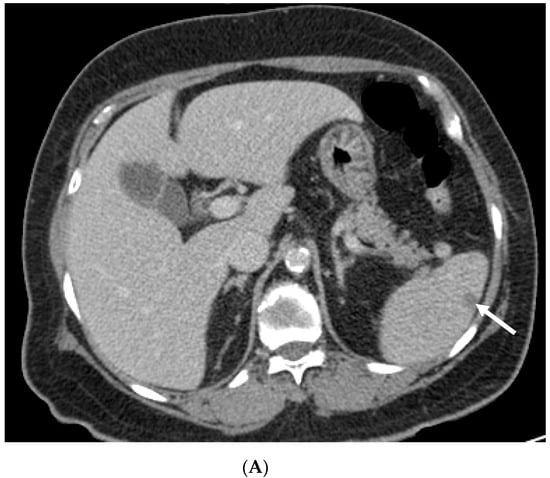

Figure 1.

Abdominal computed tomography (CT) image. (A) Axial CT image on day 1, illustrating wedge-shaped splenic infarcts (white arrow). (B) Axial CT image 2 months later, showing an improved splenic infarction.

A 74-year-old female patient presented to the emergency department of Kyung Hee University Medical Center because of dizziness and generalized weakness that started 2 days prior. The patient had a history of old cerebral infarction and was taking oral medications for hypertension and dyslipidemia. Brain magnetic resonance imaging (MRI) revealed an acute focal infarction in the right basal ganglia. At that time, in the laboratory examinations, the erythrocyte sedimentation rate (ESR) was 74 mm/h (normal range, <20 mm/h) and C-reactive protein (CRP) level was 6.61 mg/dL (<0.5 mg/dL) Aspirin was prescribed to the patient. One month later, the patient was admitted to our neurology clinic because of weakness in her left arm and numbness in both hands. MRI revealed no diffusion-restricted lesion in the brain. Physical examination revealed no remarkable findings except for paresthesia in the left hand. The patient’s motor power of four limbs were normal (grade 5). Her initial chest radiograph was normal. Her laboratory examination results showed a white blood cell count of 9.79 × 109/L (76% neutrophils), ESR of 120 mm/h, and CRP level of 18.44 mg/dL. However, she had no fever. Her serum creatinine level (0.92 mg/dL) and estimated glomerular filtration rate (GFR; 63.59 mL/min per 1.73 m2) were within the normal ranges. No proteinuria was identified. Chest computed tomography (CT) and abdominal CT were performed to exclude hidden malignancy. Chest CT revealed a subpleural nodule measuring approximately 1.5 cm in the right lower lobe. Abdominal CT revealed multiple small ill-defined low-attenuated lesions in the spleen nodules (Figure 1). Her thrombophilia screening test result was negative. The Padua prediction score was 2, in the low risk.Her echocardiography was normal and 24-hour Holter monitoring revealed normal sinus rhythm. Nerve conduction tests revealed sensorimotor polyneuropathy. The myeloperoxidase (MPO)-ANCA test result was positive (5.10 index). Percutaneous needle biopsy of the pulmonary nodule was performed first; however, the pathological results showed only focal acute inflammatory cell infiltration, with no evidence of malignancy. The second biopsy of the sural nerve demonstrated perivascular inflammatory cell infiltration and necrotizing vasculitis. These findings were consistent with vasculitic peripheral neuropathy. By considering the results of the MPO-ANCA test and the pathological profile of the sural nerve, the patient was diagnosed as having MPA-associated neuropathy with a splenic infarction and pulmonary inflammatory nodule. She received steroid pulse therapy (methylprednisolone, 125 mg/day for 3 days) on day 20 of hospitalization, followed by cyclophosphamide (500 mg/m2 every 4 weeks for six doses) with steroid maintenance therapy. She showed improvement after the steroid therapy. Her ESR level decreased to 49 mm/h and the CRP level decreased to 0.5 mg/dL. The peripheral numbness subsided slowly. After 1 month, the patient’s pancreatic enzyme levels (amylase, 192 U/L (23–85 U/L) and lipase 346 U/L (0–160 U/L)) were elevated without abdominal pain. Abdominal CT was performed to evaluate for pancreatitis and revealed improvement of the splenic lesion such as the infarction. The patient had an uneventful course for 5 months after the treatment.This study was approved by the Institutional Review Board (IRB) of Kyung Hee Medical Center, and the requirement for informed consent was waived (IRB 2020-12-083).